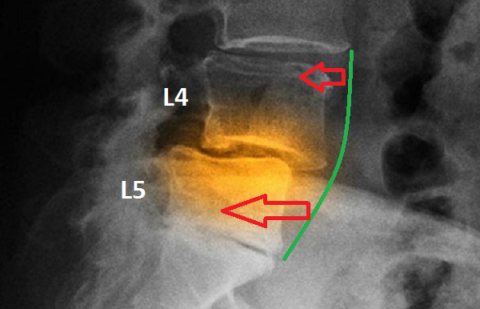

Ретролистез – это смещение тела позвонка относительно его центральной вертикальной оса назад. При этом происходит нарушение целостности удерживающих его фасеточных суставов, коротких желтых связок. Эти образования при длительном неправильном положении позвонка подвергаются грубой рубцовой деформации. Может развиваться анкилоз межпозвоночного сустава, протрузия диска, рубцевание связки. Это в будущем будет препятствовать полноценному восстановлению физиологической структуры позвоночного столба.

Ретролистез L5 – это самая распространенная форма патологии. На данный позвонок приходится максимальная физическая и амортизационная нагрузка при ходьбе, беге, статическом положении тела человека в пространстве. Расположенные здесь корешковые нервы отвечают за иннервацию нижних конечностей. Поэтому первым характерным клиническим признаком может быть воспаление седалищного нерва, боль в области лодыжки, бедра и голени одновременно. При проведении рентгенографического исследования в боковой проекции видно выдвижение пятого поясничного позвонка, который сужает спинномозговой канал. При выраженной степени смещения происходит нарушение проводимости спинномозгового канала.

Проведение рентгенографии в боковой проекции позволяет обнаружить смещение тел позвонков

Частой является ситуация, когда после травмы или другого заболевания пациенту была проведена рентгенография позвоночника, на которой обнаружено смещение позвонка. Это позволяет обнаружить ретролистез на ранней стадии.

- Рентгенография позвоночника – в большинстве случаев этой методики вполне достаточно, чтобы подтвердить наличие смещения.